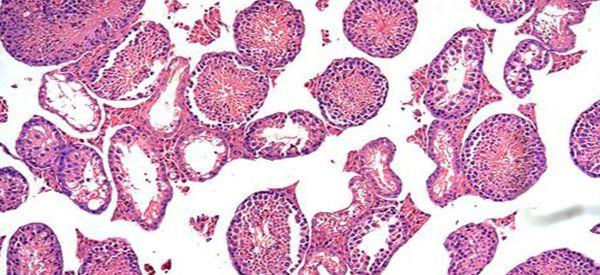

导致男性没有生精细胞的原因不排除是非梗阻性无精症、睾丸发育不良或是双侧隐睾导致的,建议你最好是先去医院做个生精细胞检查并确诊诱因,然后再根据诱因进行治疗,另外,不同程度的病情,在治疗时也会考虑到,例如患病程度不同、病程时间长短不同等,那么在治疗方式上也就有区别。

没有生精细胞也有可能是天生的,但更多的是后天由于染色体或是生殖器感染所致,这些不同诱因,在治疗时采用的方法都有区别,建议你在治疗前最好是先去医院做生精细胞检查,查出具体诱因后再进行针对性的治疗。

无生精细胞的男性,睾丸是不会产生精子的,所以也就没有生育能力,对于这类疾病,目前在临床上也没有具体的治疗方案,建议男性不要擅自采用服药的方式进行治疗,避免吃药后出现副作用,目前而言,男性只能通过以下几种方式调理: